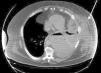

A morbidly obese 49-year-old male, current smoker, with poorly controlled diabetes mellitus type 2, presented due to left costal blunt trauma caused by an impact from the horn lateral surface of a charging bull, 30 days before his admission to the hospital. The patient did not attend emergency services at the time of trauma. He had a hematoma in the left chest wall and chest pain, which did not improve with standard analgesia. On arrival to the emergency room, blood pressure was 140/86mmHg, heart rate 110bpm, oxygen saturation 96%, and temperature 36.5°C. Physical examination revealed a hematoma in left lateral chest wall with no surrounding cellulitis and decreased breath sounds in the left hemithorax. Blood tests showed leukocytosis of 32,400/mm3 with neutrophilia (92.2%), hemoglobin 10g/dl, glucose 487mg/dl, and C-reactive protein 40.3mg/dl. Left pleural effusion was detected on the chest X-ray and no rib fractures were observed. A computed tomography (CT) scan completed the study, revealing left pleural effusion that connected with a collection in the left anterolateral chest wall (Fig. 1). Empiric antibiotic therapy with piperacillin-tazobactam was initiated (4/0.5mg IV every 8h) and both collections were drained by percutaneous puncture of the chest wall and a chest tube, from which abundant purulent material was obtained. Good lung re-expansion was observed on X-ray. After 72h of admission, multiple orifices were observed in the left lateral thoracic wall, surrounded by purulent necrotic areas without muscle involvement, so debridement and lavage were performed under general anesthesia. Microbiological results from both the pleural fluid and thoracic abscess were positive for Streptococcus agalactiae, that was sensitive to the prescribed antibiotic. The patient was hospitalized for 40 days, during which surgical wound care continued without the need for additional interventions.

The most common location of an empyema necessitatis is, as in this case, the anterior chest wall between the midclavicular and anterior axillary line. Other locations less frequently described are the abdominal wall, the paravertebral space, the mediastinum, the breast or the diaphragm.1,2 Before the antibiotic era, most cases were caused by Mycobacterium tuberculosis and the mortality rate was 66%. The incidence has fallen significantly since antibiotics were introduced, and the most common etiologic agents have become Actinomyces israelii, Streptococcus pneumoniae, Staphylococcus aureus or Pseudomonas cepacia.3,4 In our case, the causative agent was Streptococcus agalactiae, occurring secondary to chest trauma, features that are both rare in these circumstances. The clinical presentation can vary widely and includes chest pain, soft tissue mass, cough or dyspnea. Depending on the age of the patient and his/her morbidity, it may progress to septic shock. Our case was an obese patient with poorly controlled diabetes. Both of these conditions are favorable for the development of infections with atypical etiologies and locations, due to changes in the immune system response to invading microorganisms, principally fungi and bacteria. Diagnosis is based on imaging techniques, mainly CT, revealing the continuity between the pleural collection and the abscess in the chest wall. The differential diagnosis must consider other diseases such as lymphoma, mesothelioma or endocarditis.4 Although treatment should be tailored for each patient, both antibiogram-adjusted antibiotic treatment, when possible, and surgical drainage are crucial. Drainage is required to evacuate the accumulated pus and to sterilize and close the pleural cavity, thus allowing good pulmonary mobility. Different procedures may be employed, such as closed drainage systems by tube thoracostomy, or partial costectomy, or open systems, such as open thoracostomy with the creation of a pleurocutaneous fistula that allows drainage without a tube. The timing of these treatments is not standardized, but the intravenous antibiotic should be maintained for a week and then oral treatment should be continued for 1–3 weeks, depending on the patient's clinical response.5 With the combination of both treatments, a high cure rate is achieved with a low mortality rate (less than 5%); death, if it occurs, is usually secondary to the confluence of several mechanisms. such as respiratory failure, heart failure, mediastinitis, hematogenous spread or renal failure.1